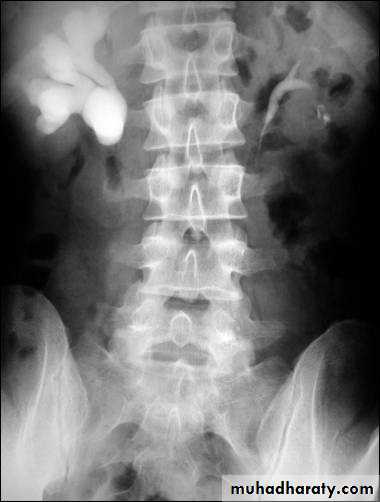

US: pre- and post-natal.IV Urography

Isotope renal scan.

CT & MRI

Pressure-Flow Study (Whitaker Test)